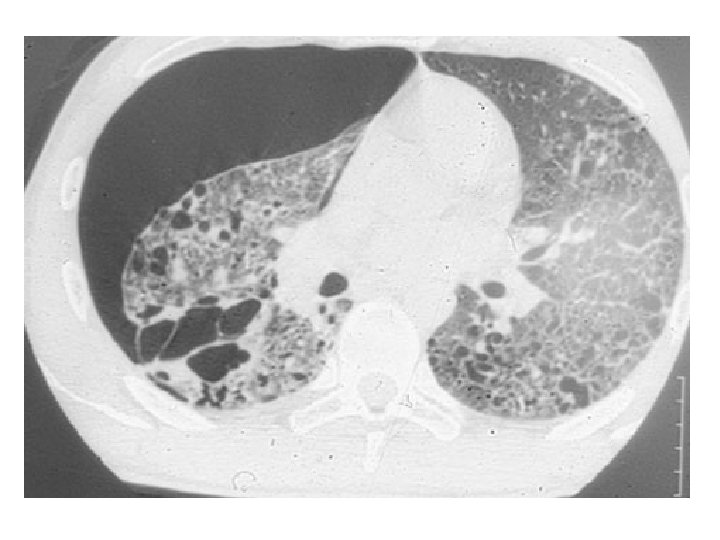

Le mésothéliome • Exposition à l’amiante dans 80% des cas, parfois très ancienne ou indirecte • Diagnostic difficile : biopsies sous thoracoscopie • Parfois asbestose connue avant • Traitement curatif rare et lourd / Palliatif – – Symphyse pleurale Chimiothérapie Radiothérapie sur le trajet des drains / antalgique Évolution loco-régionale

Poumon nécropsique après mésothéliome